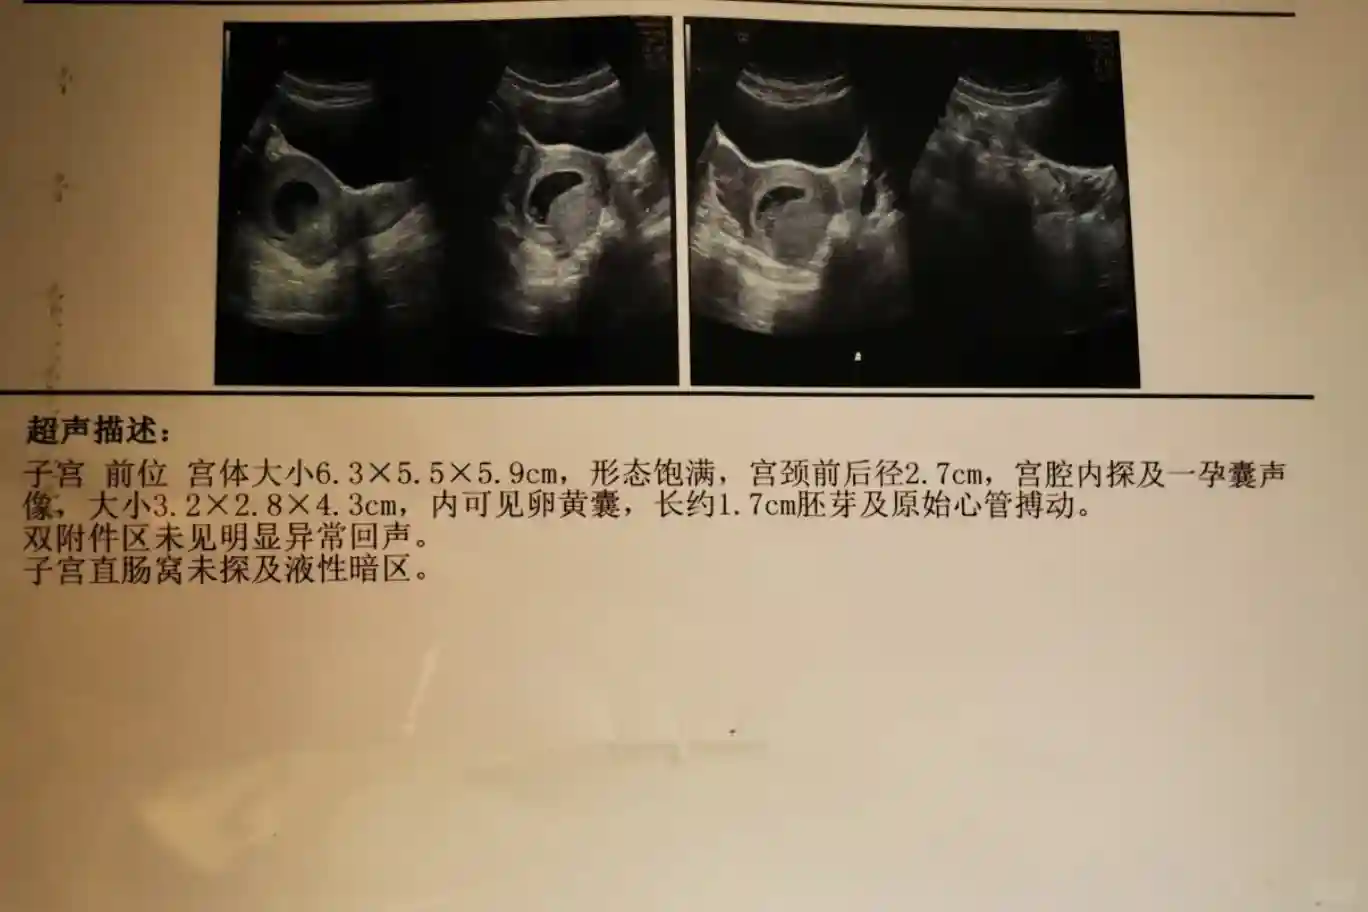

4⃣孕囊:孕8周B超孕囊长条🍆型。✅